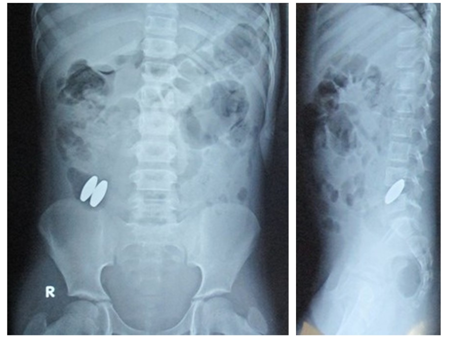

An 11 year old girl presented with a history of pain abdomen, bilious vomiting, abdominal distension and constipation of one day duration. There was a history of ingestion of 2 singing magnets 20 days back. On examination there was distension of abdomen and severe tenderness all over the abdomen along with rigidity. Abdominal radiograph showed the presence of foreign bodies in the abdomen (Figure 1). The patient was resuscitated and in view of features of peritonitis the patient was taken up for an exploratory laparotomy. Intraoperatively, bilious fluid was present in the peritoneal cavity. Multiple adhesions were present between the bowel loops. Two perforations were found in the bowel, one in the jejunum and the other in the ileum with the magnets present within the bowel near the perforations (Figures 2, 3). The perforations were caused due to the pressure necrosis caused by the presence of magnets in different loops of the bowel. The edges of perforations were freshened and perforations were closed. Peritoneal lavage was done and an abdominal drain was placed. Postoperatively the patient recovered well and the drain was removed on post operative day 5. On follow up after one month the patient was doing well.

Figure 1 Abdominal radiograph showing two magnets.